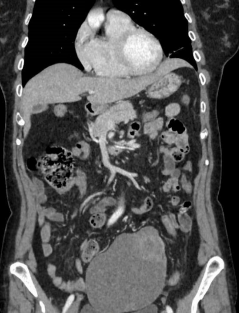

SolicitanTAC abdominal que evidencia gran masa pélvica de origen anexial izquierdo, de unos 12 centímetros, de predominio quístico, compatible con tumor ovárico epitelial (tumor borderline o adenocarcinoma mucinoso/seroso). Sin evidencia de diseminación adenopática o a distancia).